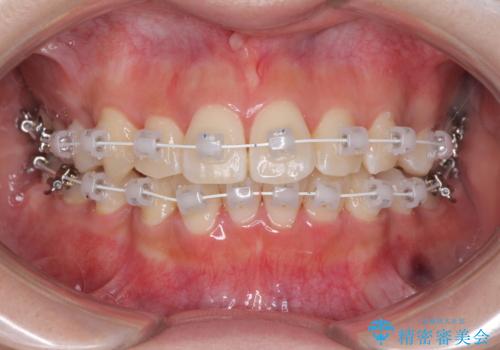

- 八重歯やデコボコをインビザラインで治療したいとのことで来院された患者様です。

インビザライン単体で治療を行うには叢生が強いと判断されたため、事前にワイヤー装置で抜歯矯正を行い、ある程度改善してからインビザラインにて仕上げていくこととしました。